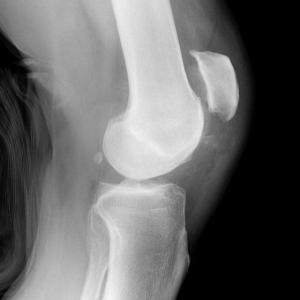

Диагностика осуществляется по рентгенограмме в 2 проекциях, но очень часто при укладке пациента на стол в рентген кабинете, наступает спонтанное вправление надколенника и зафиксировать его в положении вывиха не удается.